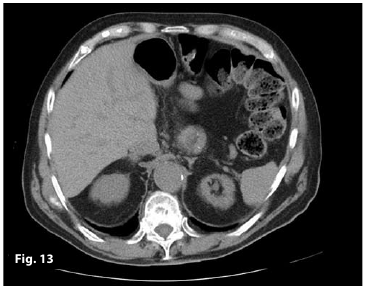

Figure13